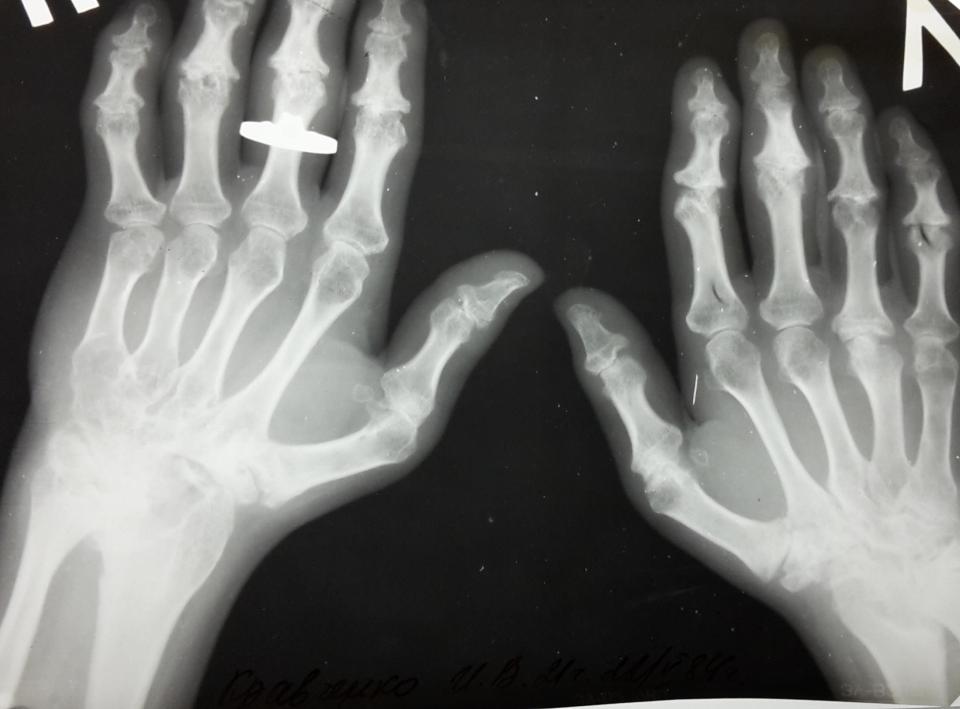

Артриты

Воспалительные изменения в суставах различной природы.

Поражение кисти при ревматоидном артрите.

Видно частичное разрушение суставных поверхностей, множественные подвывихи.